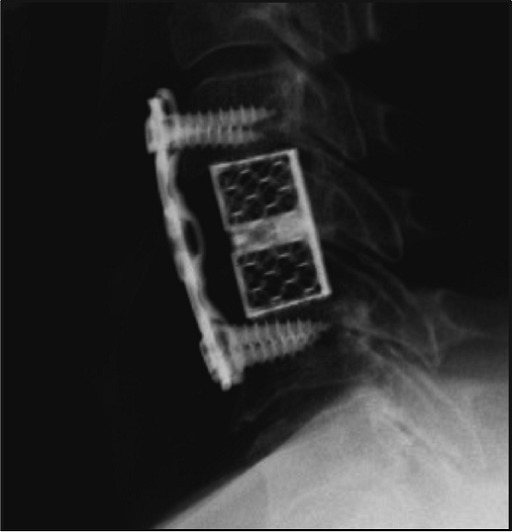

Clinical Cases

“as·C·p” plate with corpectomy prosthesis

Implanted: titanium vertebral body prosthesis supported with cervical plate asCp with cervical screws